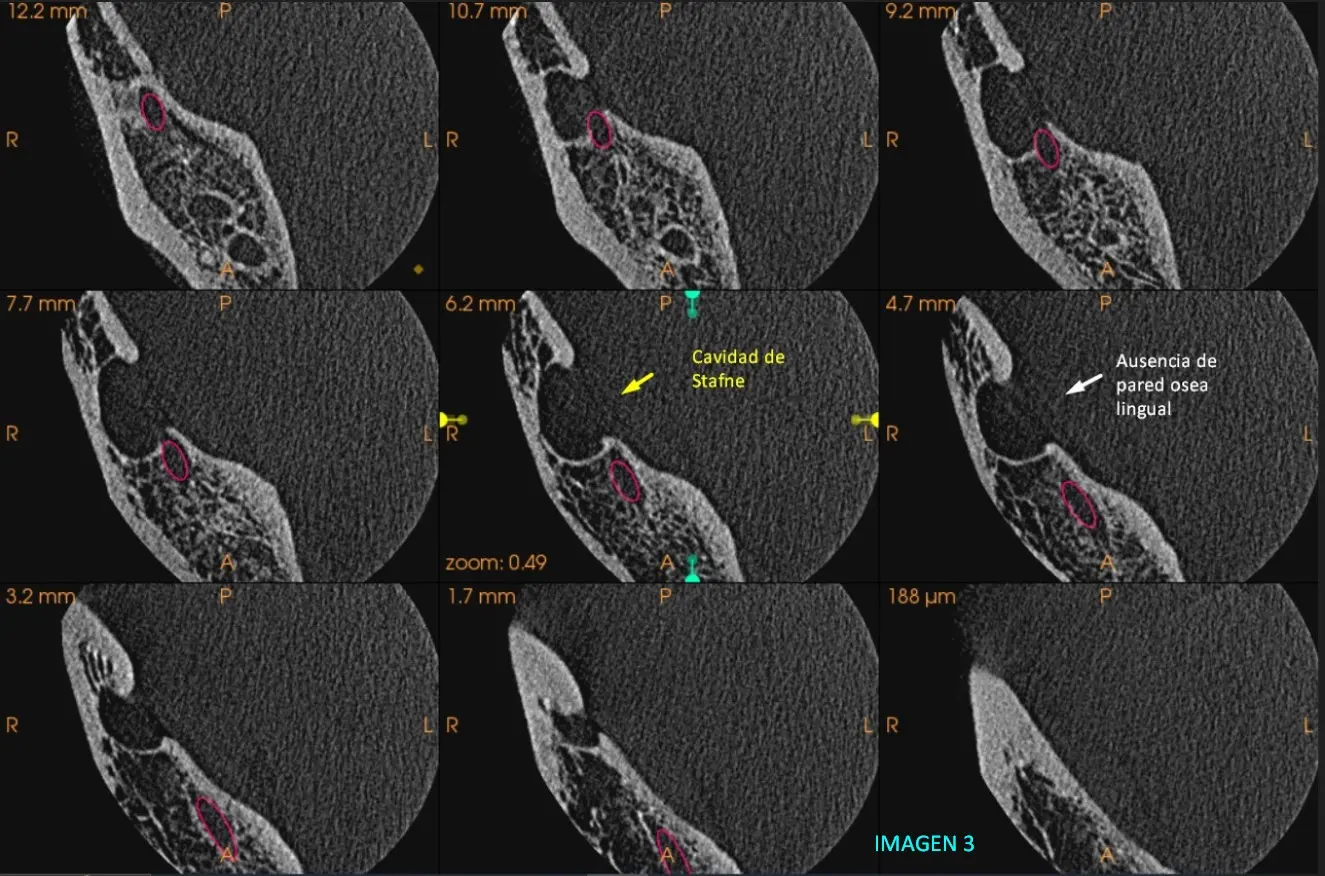

Por ende, se efectúa nuevamente una tomografía en la cual pueda abarcar la zona de interés (ángulo de la mandíbula), se realiza una Tac Cone Beam sectorizada de alta resolución zona maxilar inferior Pd 48.

Presentamos cortes transaxiales y axiales donde logramos ver imagen de forma redondeada con bordes delimitante y con densidad hipodenso la cual se encuentra en región molar cerca de ángulo de la mandíbula por debajo del conducto dentario inferior derecho y hacia cara lingual. Presenta ausencia de cara ósea lingual Imagen 2, imagen 3 e imagen 4.

Como diagnostico se llega a la conclusión de la presencia de Defecto Óseo de STAFNE, adjuntamos imagen 3D. Imagen 5

Es una variante anatómica que se presenta como depresiones en el hueso mandibular debido a un cambio en la condición anatómica, es poco frecuente, en radiografías se observa radiolúcida y bien delimitada, que usualmente se presenta en la región molar cerca del ángulo mandibular y por debajo del canal del nervio dentario inferior.

Principalmente es encontrada en radiografías de rutina como hallazgo radiográfico Frecuentemente se diagnostica erróneamente con otros tipos de patología como Quiste residual, Quiste periapical, ameloblastoma y otros. Por lo que se sugiere darle seguimiento y control atravez de radiografías.